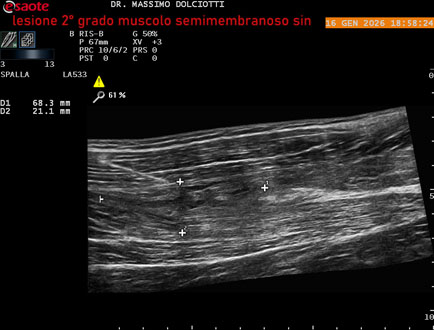

Data inserimento: 23/01/2026

Ecografia del: 16/01/2025

Strumento: Esaote MyLab Eight

Sonda: Lineare Multifrequenza 3-13 MHz

Età Paziente: M 23 anni

Motivazione dell'esame: dolore coscia sinistra da tre giornii.

Commento all'esame: le immagini ed il video documentano il muscolo semimembranoso sinistro disomogeneo per area iso-ipoecogena delle dimensioni di 38 x 14,7 mm per asse corto trasversale, 81 x 22 mm per asse longitudinale, come da lesione di 2° grado, con minimo versamento siero-ematico intramuscolare.

Conclusioni: lesione di 2° grado del muscolo semimembranoso sinistro (2nd degree lesion of the left semimembranosus muscle).